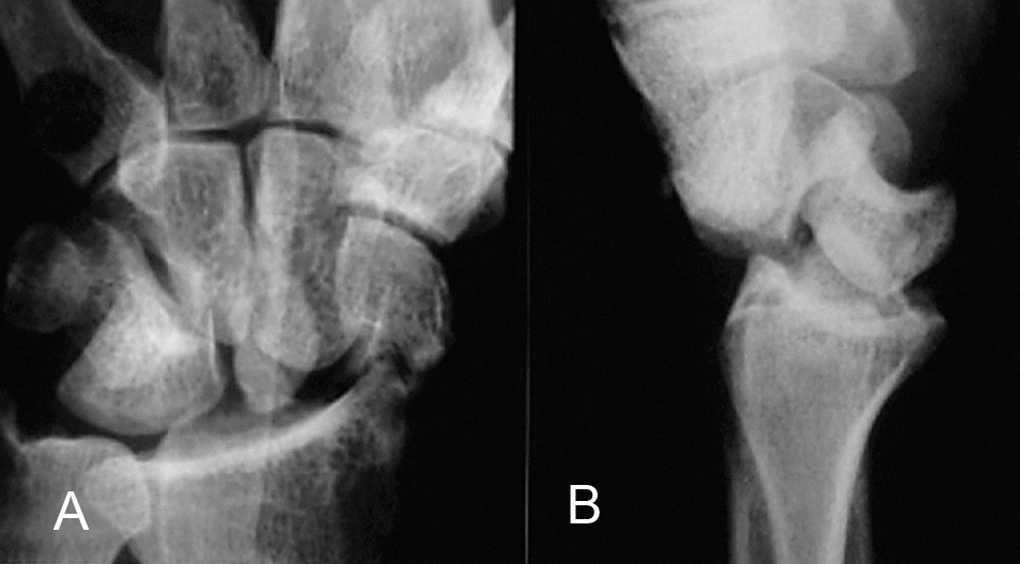

Uno de los autores (CIC)11 comenzó a emplear esta técnica, con el tornillo tipo Herbert (fig. 1), en 1989. Desde hace 6 años estamos utilizando con preferencia un tornillo de titanio de mini-fragmentos con cabeza plana (Leibinger), por las siguientes razones:

Figura 1. Radiografía preoperatoria (A) y control al año de la osteosíntesis con tornillo tipo Herbert (B).

Un punto muy controvertido es la actitud a seguir en los retardos de consolidación, sobre si limpiar el foco de fractura e injertar el mismo. Cuando el defecto óseo en las radiografías es limitado, con frecuencia es difícil localizar visualmente el foco lesional, debido a la «cicatrización» de la superficie cartilaginosa, detectable tan sólo por una línea de diferente coloración, y se necesita la ayuda del amplificador de imágenes para su confirmación. Incluso en las posiciones extremas se comprueba que ambos fragmentos se muevan conjuntamente. En estos casos, nos limitamos al simple atornillado, habiendo conseguido la consolidación en todos ellos (figs. 1 y 2).